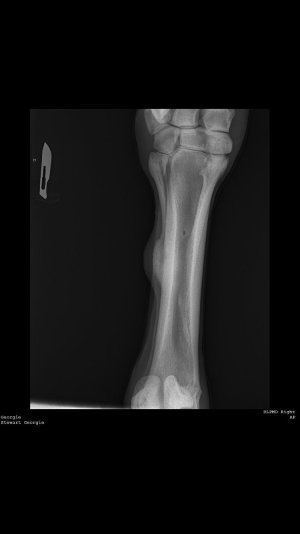

I’ve just recently bought my horse (I knew about the splint!), but it seems to be getting bigger? Apparently he threw it around Christmas time. No heat and no lameness etc. It is solid to touch, but is absolutely massive!

It is on the outside of his near fore.